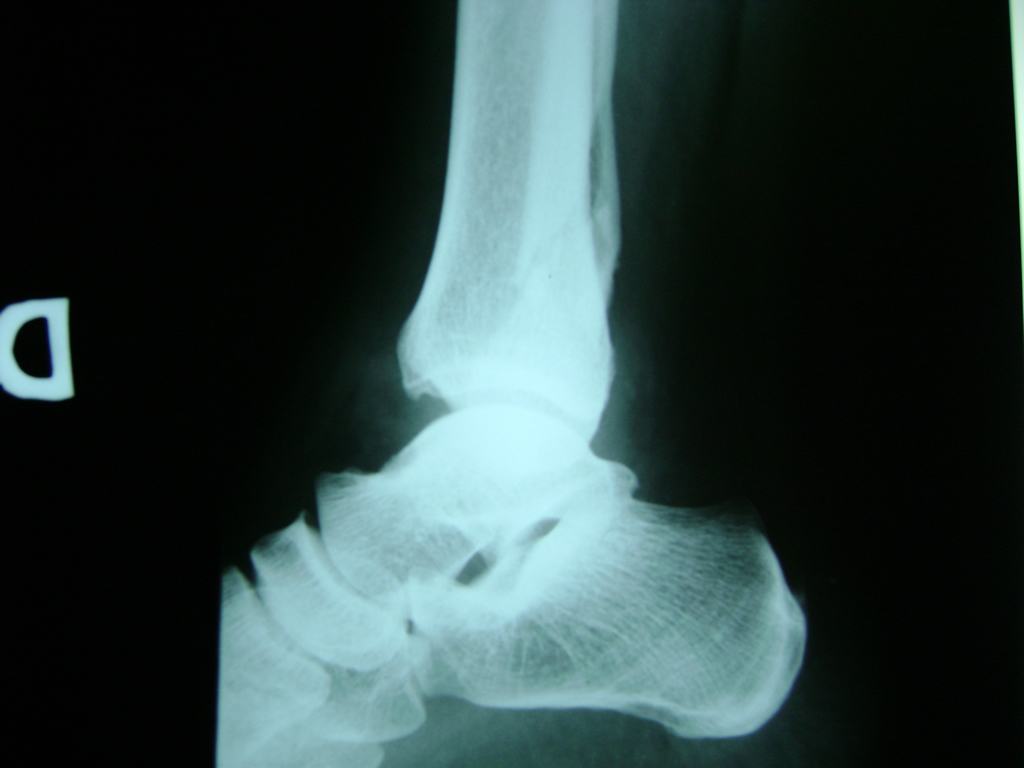

Cirugías de Peroné y Tibia

Una fractura de tobillo es la rotura de uno o más de los huesos del tobillo. Estas fracturas pueden ser:

Algunas fracturas de tobillo pueden requerir cirugía si:

Cuando se necesita cirugía, es probable que esta implique el uso de clavijas de metal, tornillos o placas para sostener los huesos en su lugar mientras la fractura se consolida. Los elementos de soporte pueden ser temporales o permanentes.